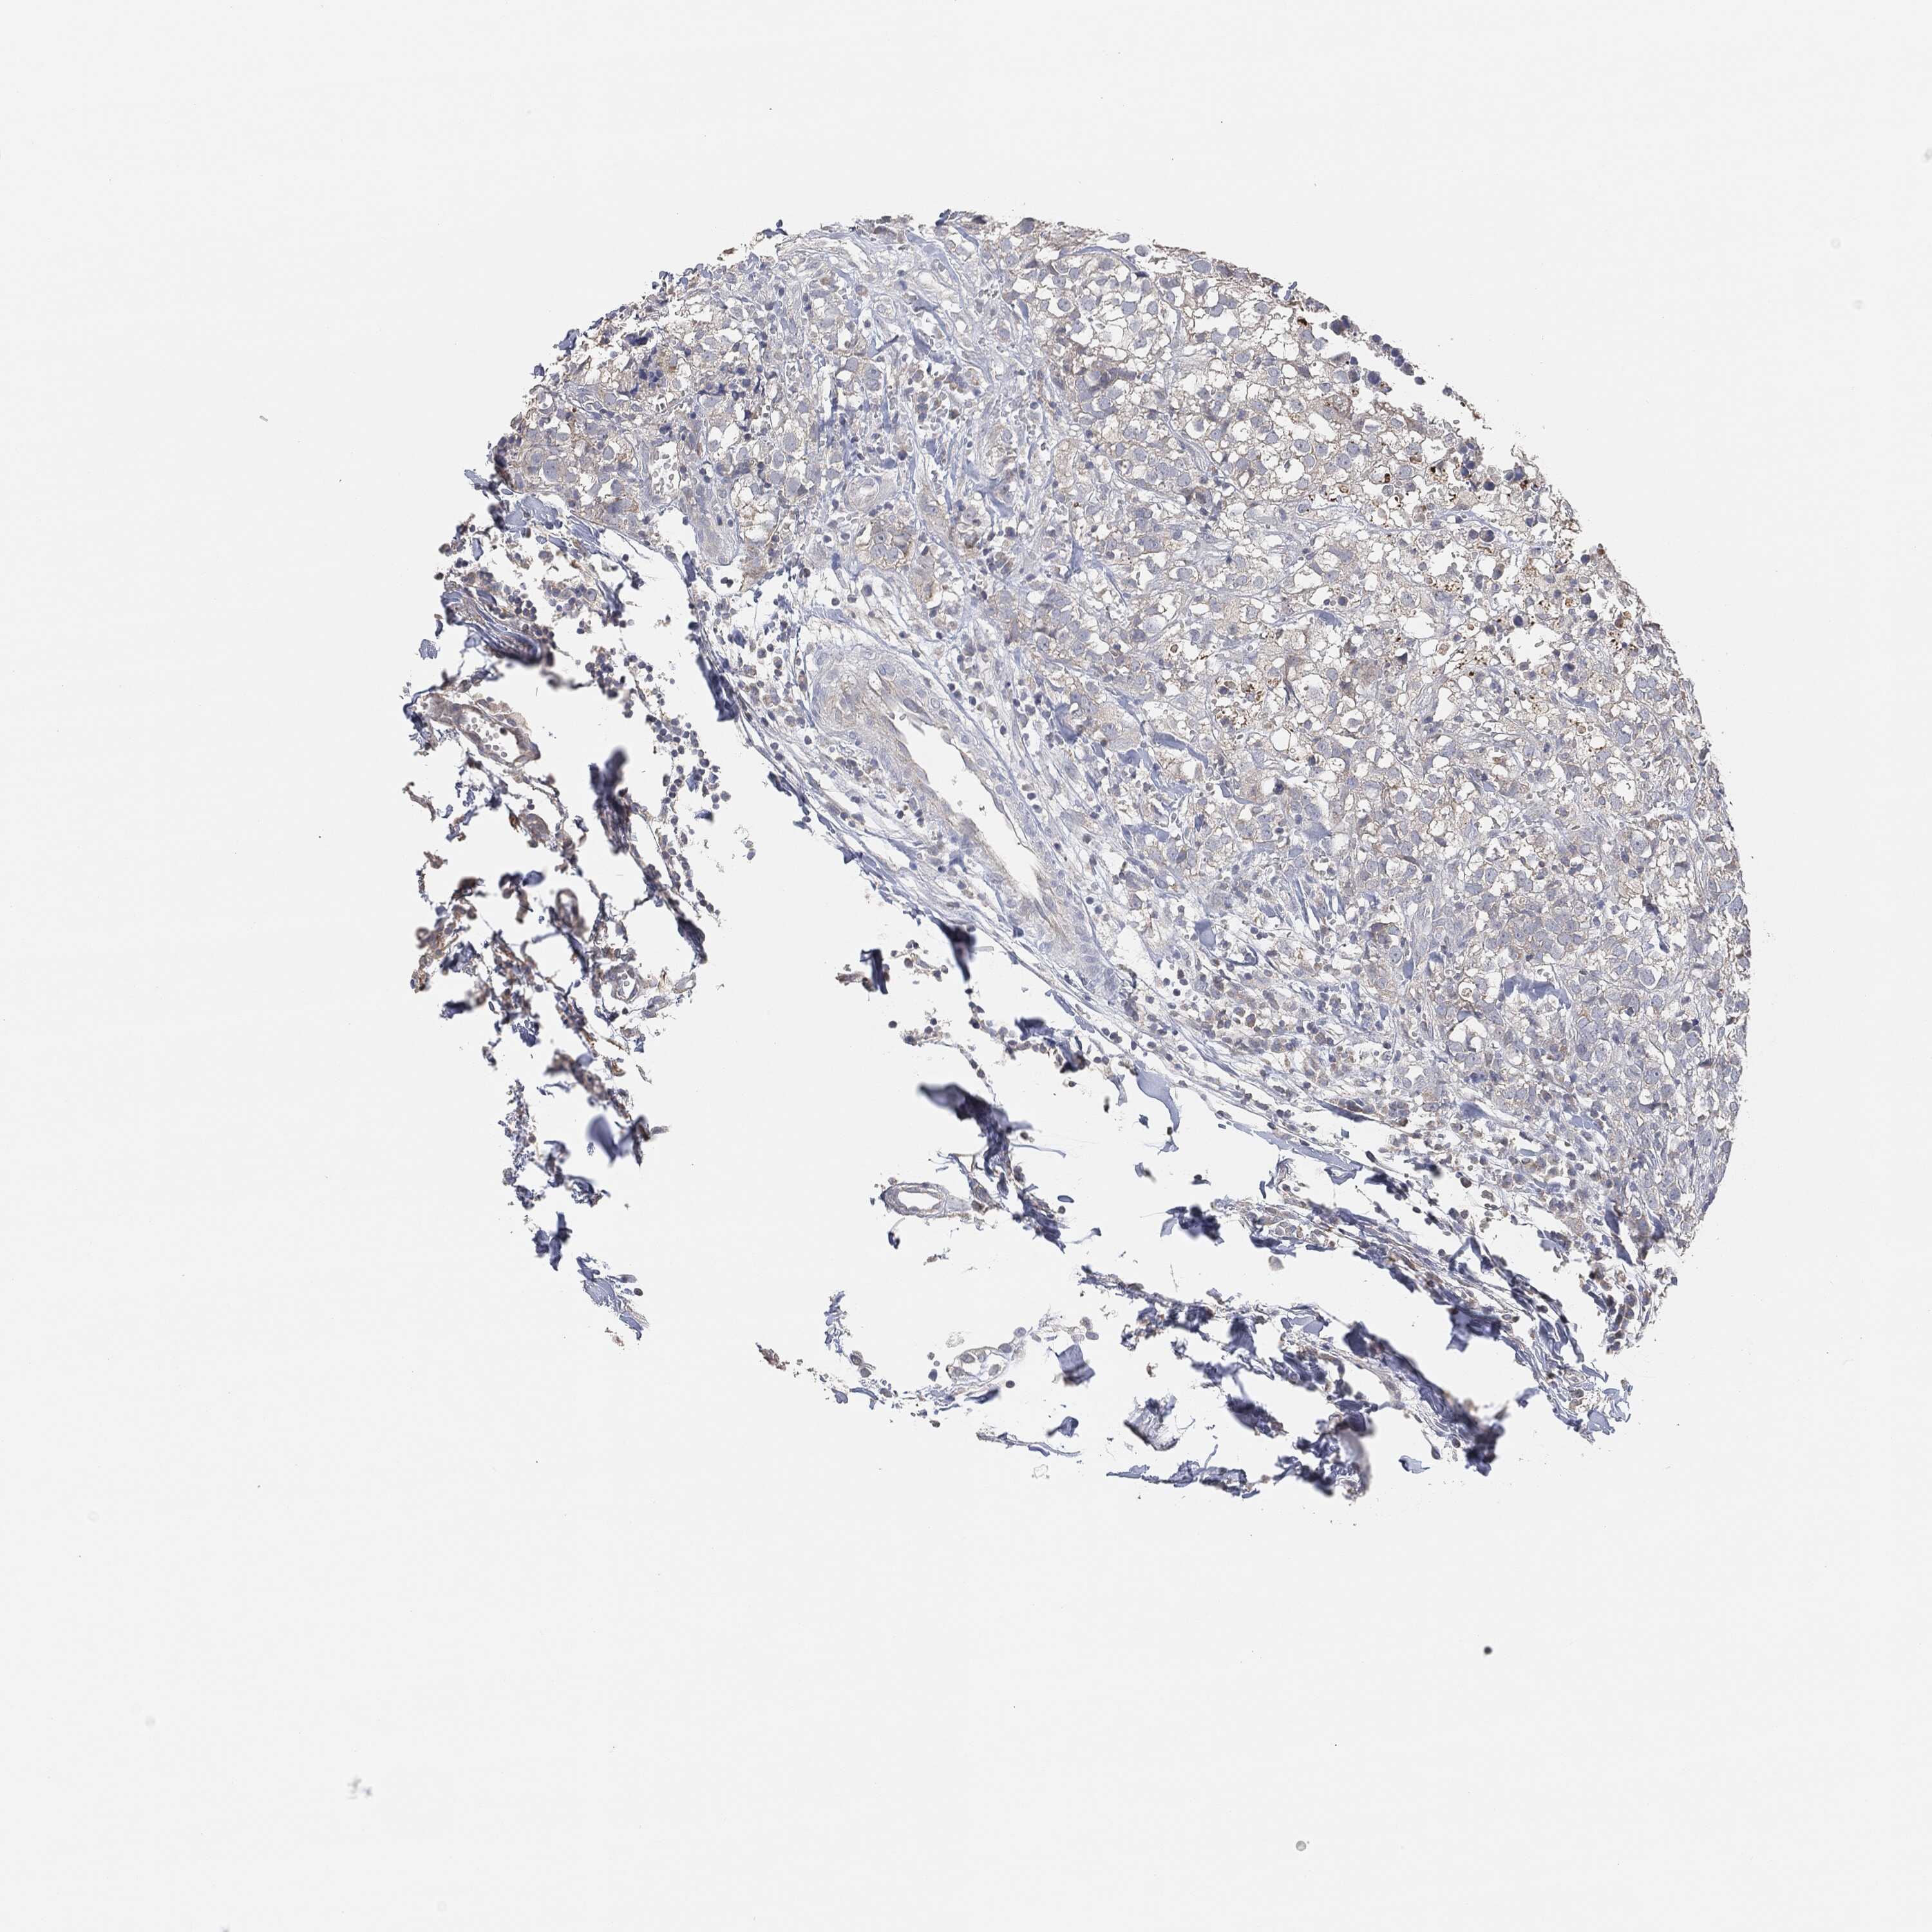

BRCA TCGA BRCA VALIDATION PROTEIN EXPRESSION

ANTIBODIES

AND

VALIDATION